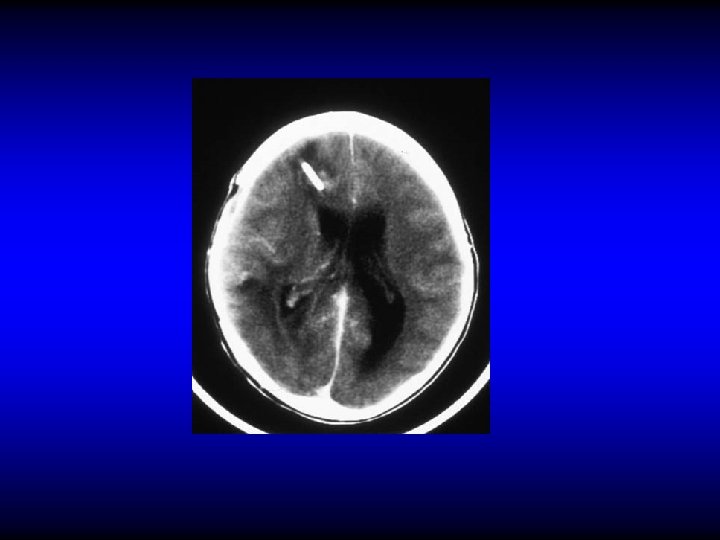

Subdural abscess (empyema) • Suppuration of the subdural space • Sever headache, fever, irritative and paralytic focal neurological symptoms • CT and MRI

Subdural abscess (empyema) • Suppuration of the subdural space • May be localized, multiple or diffuse • Sever headache, fever, irritative and paralytic focal neurological symptoms • CT and MRI • Treatment is by neurosurgical drainage